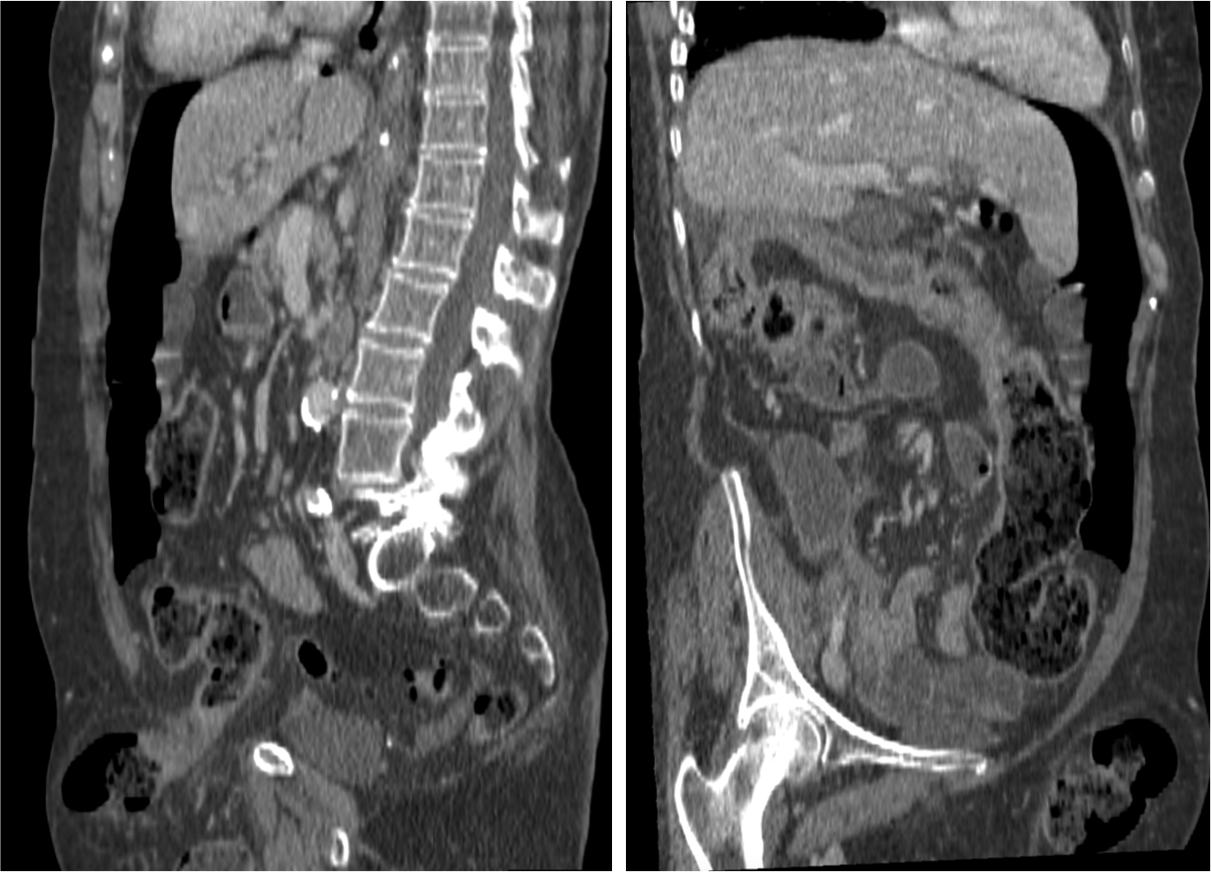

El diagnóstico actual de la se realiza mediante TC abdominal:

- El hallazgo patognomónico es el signo de la escarapela o diana identificable en la TC o ecografía.

- Podemos ver la imagen de “Intestino dentro de intestino” gracias a las reconstrucciones multiplanares.

Invaginación de Intestino Delgado

- Son más frecuentes que las de colon

- Es más frecuente la invaginación esporádica. Si hay lesión subyacente, suele ser benigna.

- Las causas malignas son menos frecuentes (15-30%), en general metástasis, sobre todo de melanoma.

- El linfoma constituye el 20-40% de todos los tumores malignos de ID.

Invaginación de Intestino Grueso

- Suele deberse a una lesión subyacente, sobre todo procesos malignos primarios.

- Resto son causas benignas (lipomas, polipos adenomatosos) o idiopáticas.

- Díficil determinar la causa subyacente, excepto en el lipoma (atenuación grasa) o si existe enfermedad metastásica abdominal conocida.

- El lipoma constituye la causa benigna más frecuente de invaginación colo-cólica y el adenocarcinoma de colon la causa maligna más frecuente.